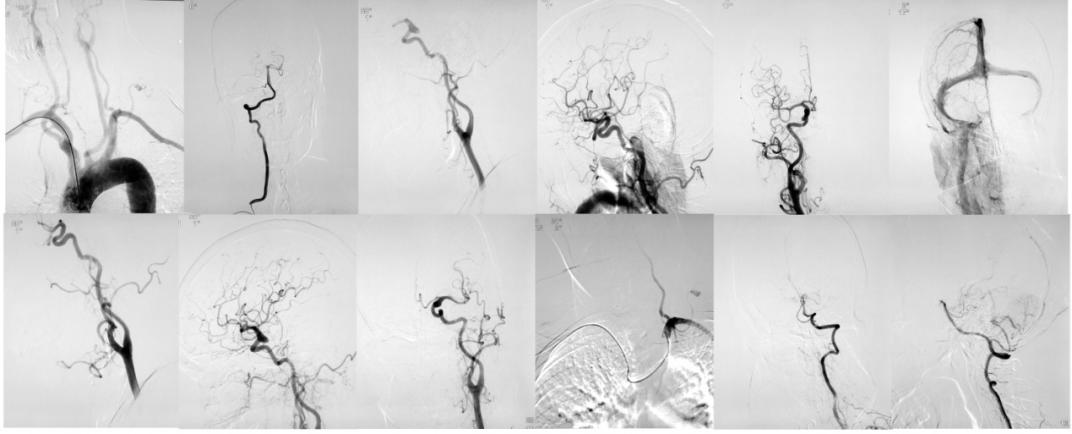

全脑血管造影术(DSA)是医学界公认的脑血管疾病诊治的“金标准”。它不但能清晰明确地了解影像病变而且在造影过程中就可了解血管内血流、血管壁等情况,全面判断血管结构及功能变化。使用显影剂后可使血管影像更为清晰并能发现被骨质结构所掩盖的微小病变,为确诊和治疗脑卒中提供了可靠的依据。

我院是广西率先开展脑血管病介入治疗的医院之一,多年来我科在该技术的临床应用方面取得了丰富的经验。无论是在高危患者及复杂手术的治疗上均获得了较好的临床疗效。其中神经内科一病区(脑病一区)是国家中医药管理局重点脑病专科、国家中医药管理局重点瘘病协作组副组长单位、广西中西医结合脑病医疗中心,是集医疗、教学、科研于一体的重点临床科室。

神经内科一区主任、神经内科学科带头人罗宁博士已研发出新型经桡动脉全脑血管造影导管并获得国家专利,临床使用中取得很好的效果,该专利已与国内知名公司取得合作协议,在临床得到很好的推广。